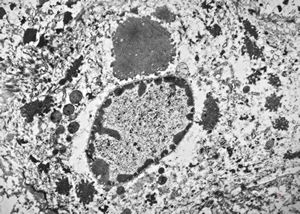

F, 57y. | mycosis fungoides … cerebriform nucleus of Sézary cell